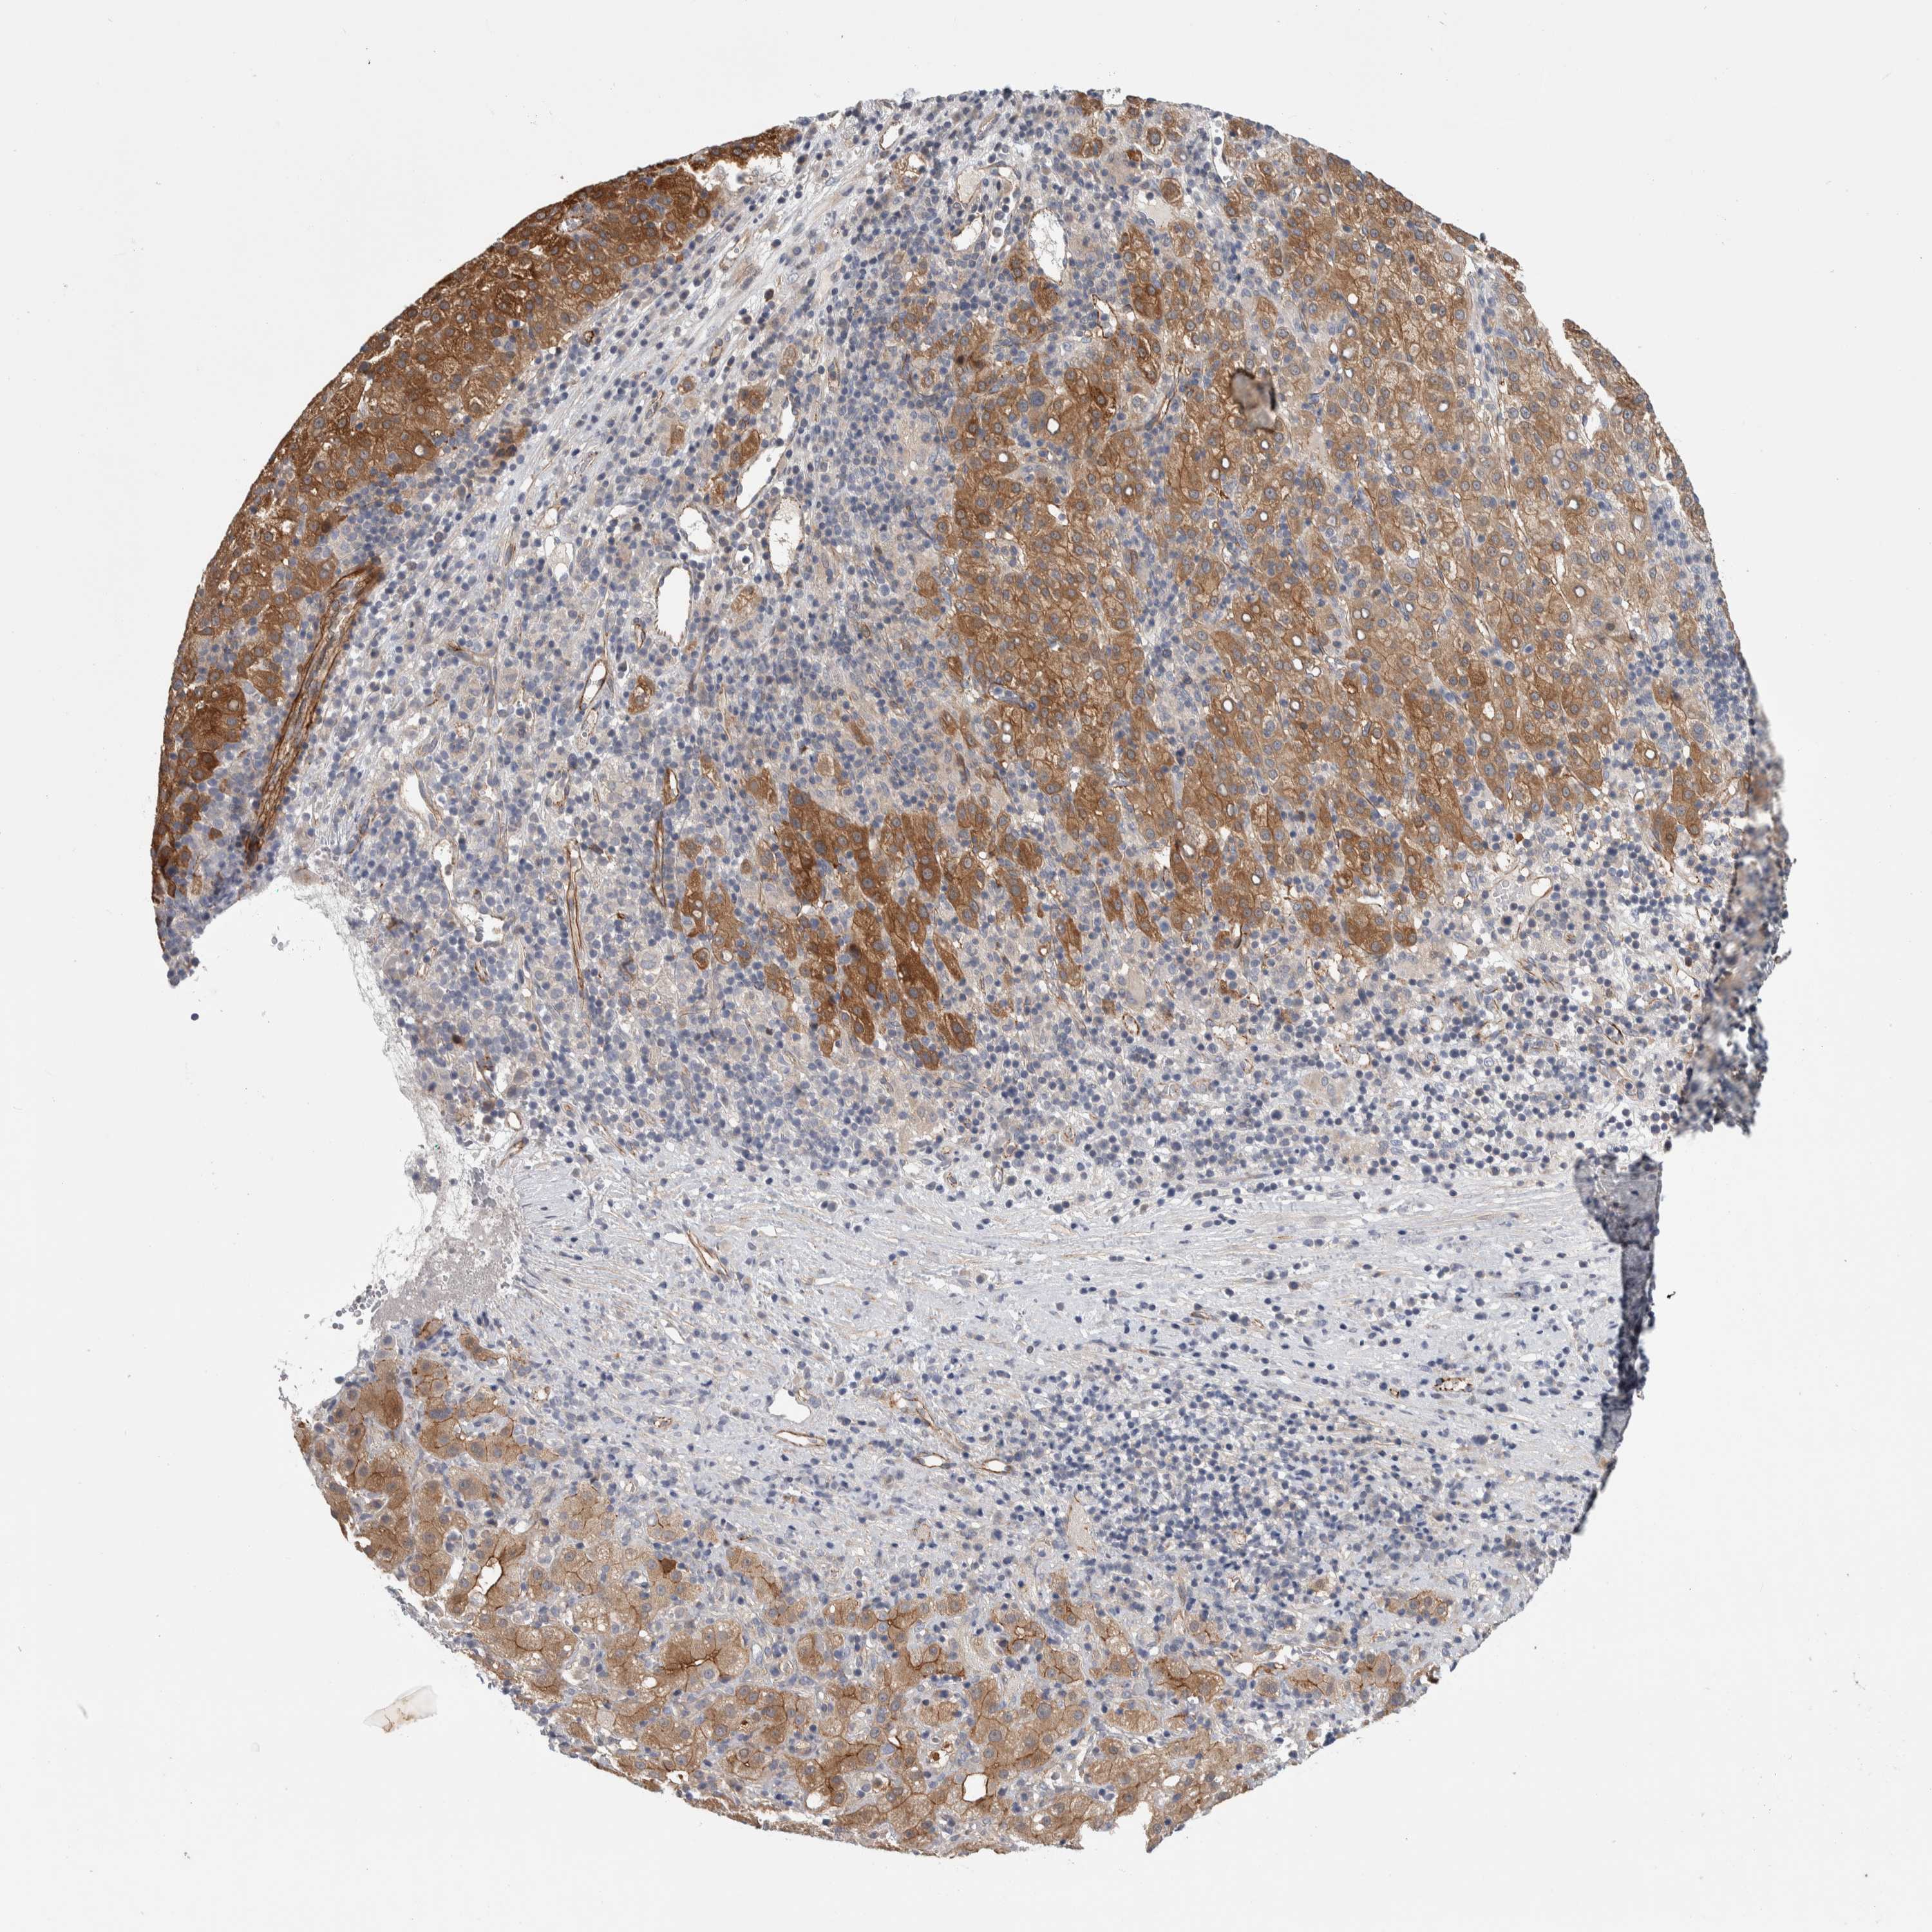

LIVER CANCER - Protein expressioni

A mouse-over function shows sample information and annotation data. Click on an image to view it in a full screen mode. Samples can be filtered based on level of antibody staining by selecting one or several of the following categories: high, medium, low and not detected. The assay and annotation is described here.

Note that samples used for immunohistochemistry by the Human Protein Atlas do not correspond to samples in the TCGA dataset.

Antibody stainingi

Antibody staining in the annotated cell types in the current human tissue is reported as not detected, low, medium, or high, based on conventional immunohistochemistry profiling in selected tissues. This score is based on the combination of the staining intensity and fraction of stained cells.

Each image is clickable and will lead to virtual microscopy that enables deeper exploration of all samples and also displays staining intensity scores, fraction scores and subcellular localization as well as patient and tissue information for each sample.

Antibody HPA024154

Staining

High

Medium

Low

Not detected

Intensity

Strong

Moderate

Weak

Negative

Quantity

>75%

75%-25%

<25%

None

Location

Nuclear

Cytoplasmic/membranous

Cytoplasmic/membranous,nuclear

Cholangiocarcinoma

Carcinoma, Hepatocellular, NOS